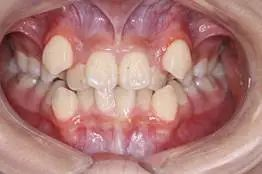

3、牙齒前突:當(dāng)前牙的傾斜度不良,無論是外突,還是向內(nèi)傾斜,都會(huì)影響到牙齒和面部的美觀。如圖3所示的上牙前突,上下前牙之間咬合距離大,專業(yè)術(shù)語就是深覆蓋。如圖3所示.

3,上前牙外突,唇向傾斜,上下牙之間咬合距離大